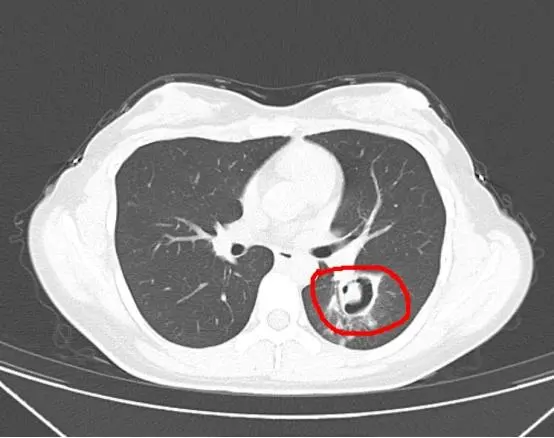

女子清理发霉衣柜后,竟查出肺部被曲霉菌感染

竟查出肺部被曲霉菌感染